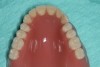

Figure 17 Occlusal view of the final denture.

Figure 17

Figure 18 Intaglio surface of the final denture.

Figure 18